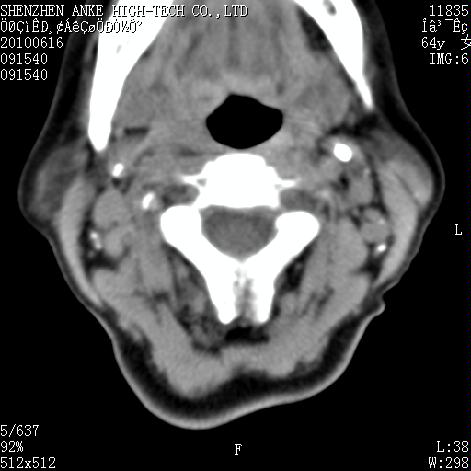

标题: CT27132:患者女,64岁,颈部及全身多处包块,现觉吞咽困难4 [打印本页]

标题: CT27132:患者女,64岁,颈部及全身多处包块,现觉吞咽困难4

右侧甲状腺癌伴右颌下腺淋巴结转移

右侧甲状腺癌伴淋巴结转移

增强看看 甲状腺癌

右侧甲状腺癌伴右颌下腺淋巴结转移!建议增强!